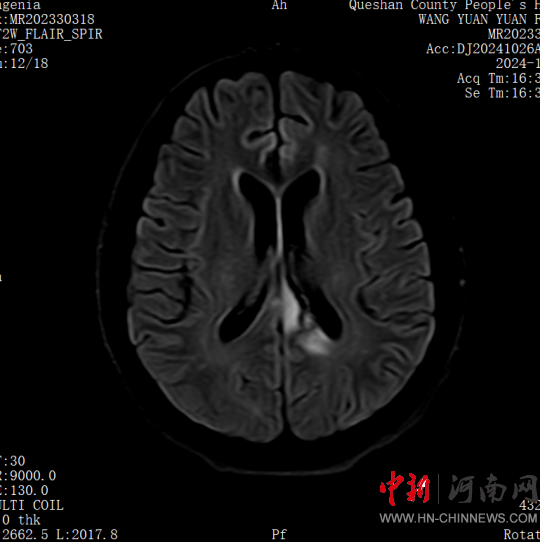

患者,女,32歲,車禍傷,到達(dá)確山縣人民醫(yī)院急診科創(chuàng)傷中心救治時血壓80/45mmHg,心率115次/分,處于昏迷、休克狀態(tài),病情危重。急診科迅速啟動創(chuàng)傷中心急救綠色通道,醫(yī)護(hù)人員立即展開搶救,積極抗休克治療的同時,聯(lián)系神經(jīng)外科、胸外科、急診重癥監(jiān)護(hù)室緊急會診,同時快速CT、床旁FAST檢查明確診斷。通過一系列急救措施,患者的休克狀態(tài)稍微好轉(zhuǎn),經(jīng)多學(xué)科會診后明確診斷為:多處損傷并失血性休克、彌漫性軸索損傷、蛛網(wǎng)膜下腔出血、腦挫傷、股骨及脛腓骨粉碎性骨折、多發(fā)肋骨骨折并肺挫傷、腰椎骨折。ISS評分高達(dá)50分,死亡率極高,患者病情危重,立即送入急診重癥監(jiān)護(hù)室進(jìn)行高級生命支持治療。